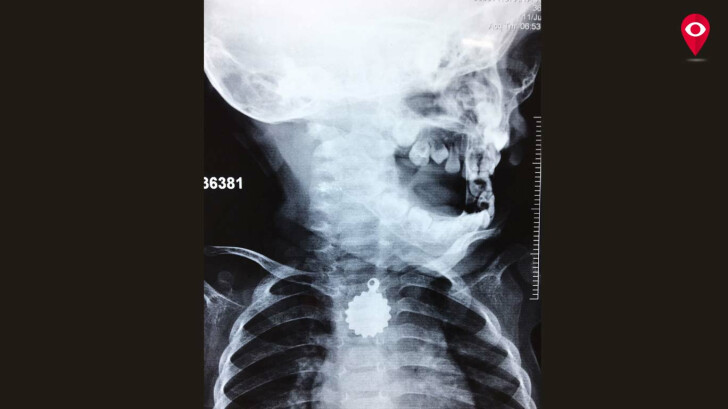

जोगेश्वरी में रहनेवाली रुकय्या खान नाम की बच्ची ने खेल खेल में ही एक लॉकेट को अपने गले में अटका लिया। बच्ची के गले में लॉकेट अटकने के बाद रुकय्या के मां बाप काफी परेशान हो गए थे। बच्ची को कूपर अस्पताल में भर्ती कराया गया जहां डॉक्टरो ने बिना किसी ऑपरेशन के एन्डोस्कोपी तकनीक की मदद से ही उस लॉकेट को बच्ची के गले से बाहर निकाला।

रुकय्या को कूपर अस्पताल में भर्ती कराया गया। डॉ. शशिकांत मशल ने बच्ची को ऑपरेशन थिएटर में ले जाकर एन्डोक्सोपी तकनीक से बच्ची के गले से लॉकेट बाहर निकाला। डॉ. शशिकांत मशल का कहना है की जब बच्ची को अस्पताल में भर्ती कराया गया तब लॉकेट बच्ची के अन्ननलिका में फसा हुआ है।

लॉकेट का हिस्सा धारदार होने के कारण हमे उसे बिना ऑपरेशन के एन्डोस्कोपी तरिके से बाहर निकालना पड़ा।